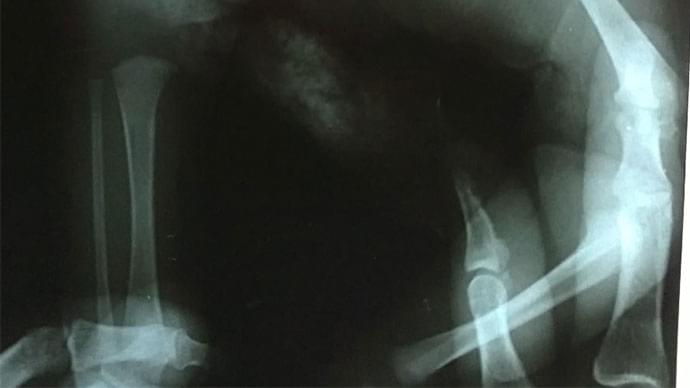

Ortopedia Infantil